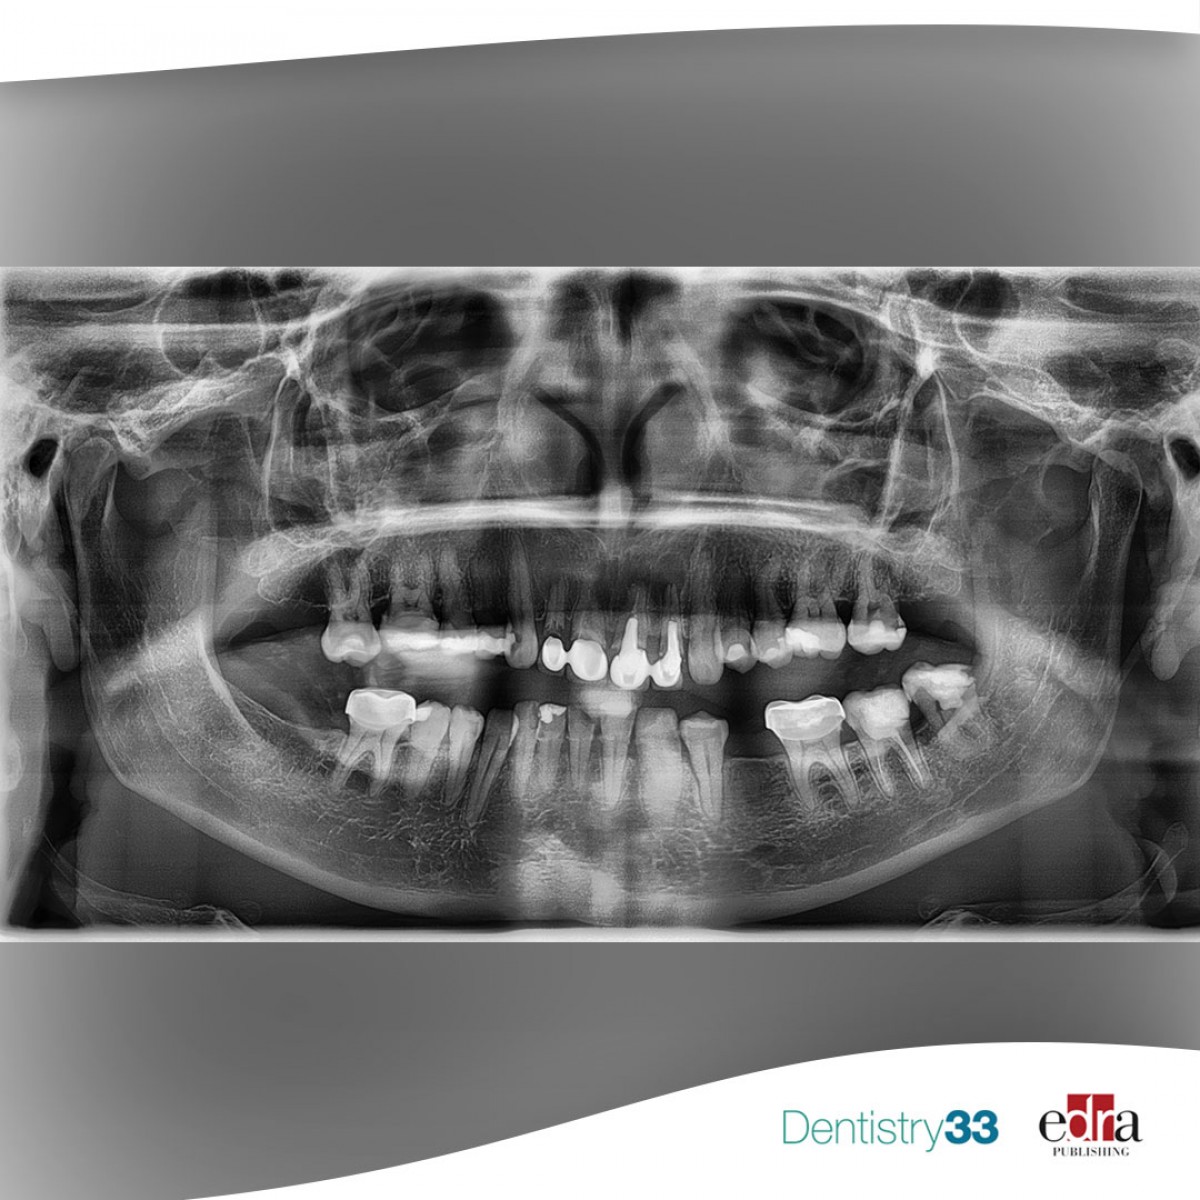

Chronic intake of systemic drugs and impact on the healing of endodontic pathologies

The association between systemic health and the pathogenesis or healing of endodontic disease has gained much attention over the past two decades.

Several literature studies have documented this correlation especially in cases of chronic diseases such as diabetes mellitus (DM), cardiovascular disease (CVD), kidney disease, gastrointestinal disease and rheumatoid arthritis.

Recent systematic reviews have recognized the relationship between endodontic success and various systemic diseases, including DM, CVD, human immunodeficiency virus infection and drugs such as oral bisphosphonate (BP). Studies have also confirmed the possible influence of DM and CVD on the outcome of endodontically treated teeth.

Most patients who have these diseases are treated for these and other conditions with potent drugs that have important biological functions, including anti-inflammatory, antimicrobial and osteoconductive functions, relevant functions in the pathogenesis or healing of pulpitis and apical periodontitis (AP).

Some drugs have been associated with an increase or decrease in the prevalence of apical periodontitis, while others have been associated with an incidence of pulp calcification or cervical root resorption.

The endodontic effects of some categories of drugs found by the authors based on the data obtained from this review are listed below.

• Statins: shown to decrease the prevalence of PsA, improve healing of PsA and increase calcifications in the vital pulp.

• BM-monoclonal antibodies against RANKL: give an increase in the prevalence of AP (not significant).

• BM-monoclonal antibodies against TNF-alpha: give improved healing of AP.

• Metformin: decreases the prevalence of AP.

• Bisphosphonates: damage decrease in the prevalence of A.

• Antiresorptive drugs-denosumab: damage increased prevalence of cervical root resorption.

• Glucocorticoids: damage increased prevalence of PsA and an increase in calcifications in the vital pulp (not significant).

Conclusions

From the data of this review, researchers concluded that systemic drugs taken chronically can affect the prevalence or recovery of endodontic diseases and conditions, but the level of evidence is still scarce. This justifies the need for future longitudinal clinical trials on the role of chronic systemic drugs as well as drug control when studying systemic diseases.